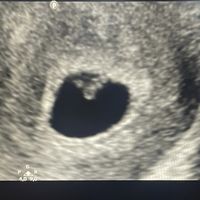

Adjunto ecografía abdominal de 13+4. A mí me a la sensación de niña, pero no estoy segura.jeje